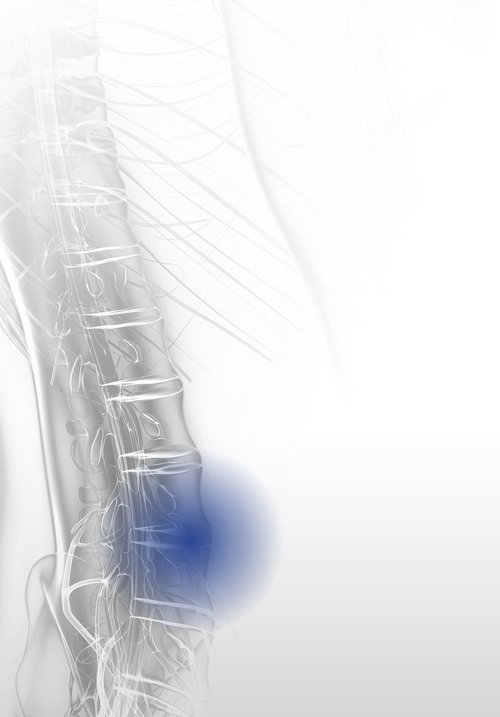

Discogenic pain syndrome is a degenerative spinal disease caused by wear and tear on vertebral discs. It begins with fluid loss in the inner core of the disc (nucleus pulposus), reducing its resilience and elasticity. This can lead to segmental instability. Sensitization of the affected area lowers the stimulus threshold, potentially resulting in chronic discogenic pain. Protruding discs may compress spinal and extraspinal nerve structures, causing radicular pain.